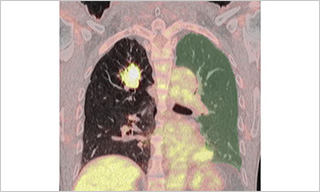

CRISPR/CasRx suppresses KRAS-induced brain arteriovenous malformation developed in postnatal brain endothelial cells in mice